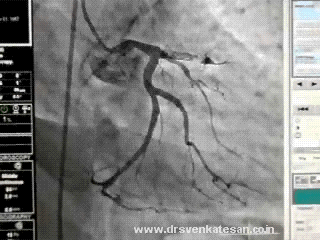

To label a left-sided pleuritic pain with ECG changes as ACS can never be considered as a serious error.However , rushing such patients to cath lab or lytic therapy along with heparin leads to more trouble. ER physicians should always keep in mind T wave inversion in isolation is indeed a rare cause* of ischemia. Still, as a physician first , we need to have a check list to rule out common non cardiac conditions. Pneumothorax is one another entity that can exactly mimic a STEMI with ST segment shifts and q waves.It’s also possible left sided pleural effusions produce q waves and mimic an old MI as this case report reveals.(Constatine A Manthous Chest 1993)